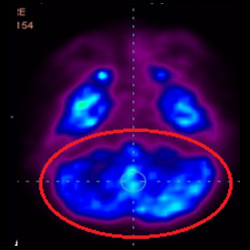

干細(xì)胞治療腦癱后改善的客觀放射學(xué)證據(jù)

細(xì)胞治療前 PET CT 掃描顯示神經(jīng)組織中的藍(lán)/黑色區(qū)域,表明腦癱引起的大腦損傷。

細(xì)胞治療后,藍(lán)色和黑色區(qū)域減少,并且看到更活躍的區(qū)域。這表明損傷減少并改善了大腦功能。

這證明細(xì)胞療法是治療腦癱兒童安全有效的方法。細(xì)胞療法可以更新大腦損傷的核心,并且可以通過 PET CT 掃描來監(jiān)測(cè)大腦的改善情況。這些細(xì)胞療法與標(biāo)準(zhǔn)治療一起促進(jìn)腦癱兒童的生長(zhǎng)和改善。